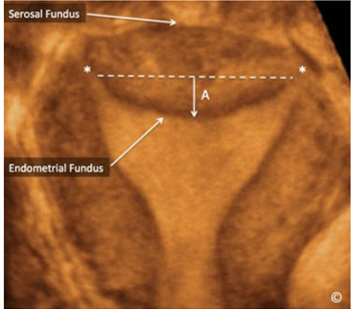

Hình 5: Hình ảnh tử cung ở mặt phẳng giữa trán trên siêu âm 3D cho thấy thanh mạc vùng đáy tử cung (serosal fundus), nội mạc vùng đáy tử cung (Endometrial Fundus) và vị trí của 2 lỗ trong vòi trứng (hoa thị).

Lưu ý rằng chỗ lõm của nội mạc vùng đáy tử cung (A) được đo từ trung điểm đường nối 2 lỗ trong vòi trứng đến điểm giữa nội mạc vùng đáy tử cung ( mũi tên A).